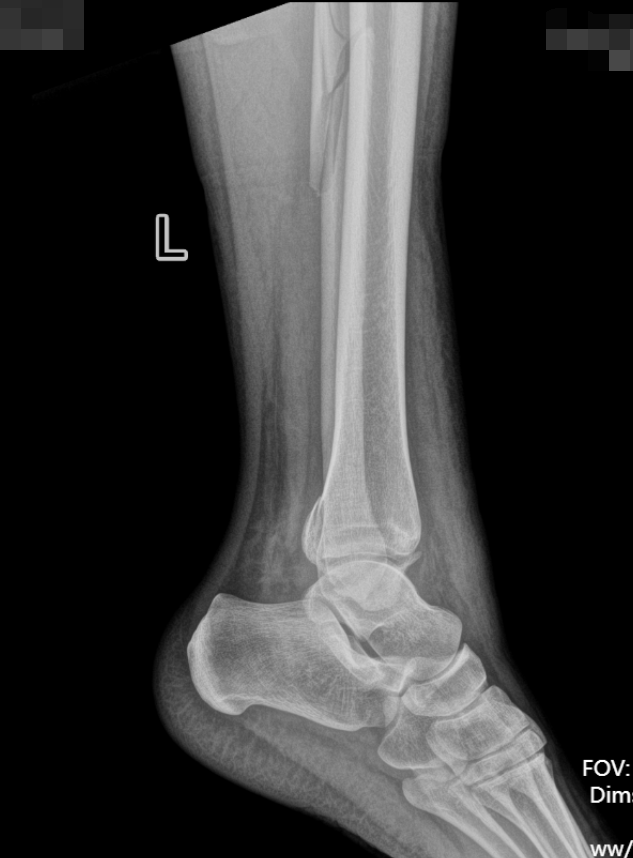

患者因意外受伤后踝关节疼痛、肿胀、无法行走,急诊就诊于我院。

经检查确诊为旋前外旋 Ⅳ 度踝关节骨折,包含腓骨中段骨折、内踝骨折、后踝骨折及下胫腓联合分离,属于临床中结构复杂、稳定性破坏较严重的踝关节损伤。